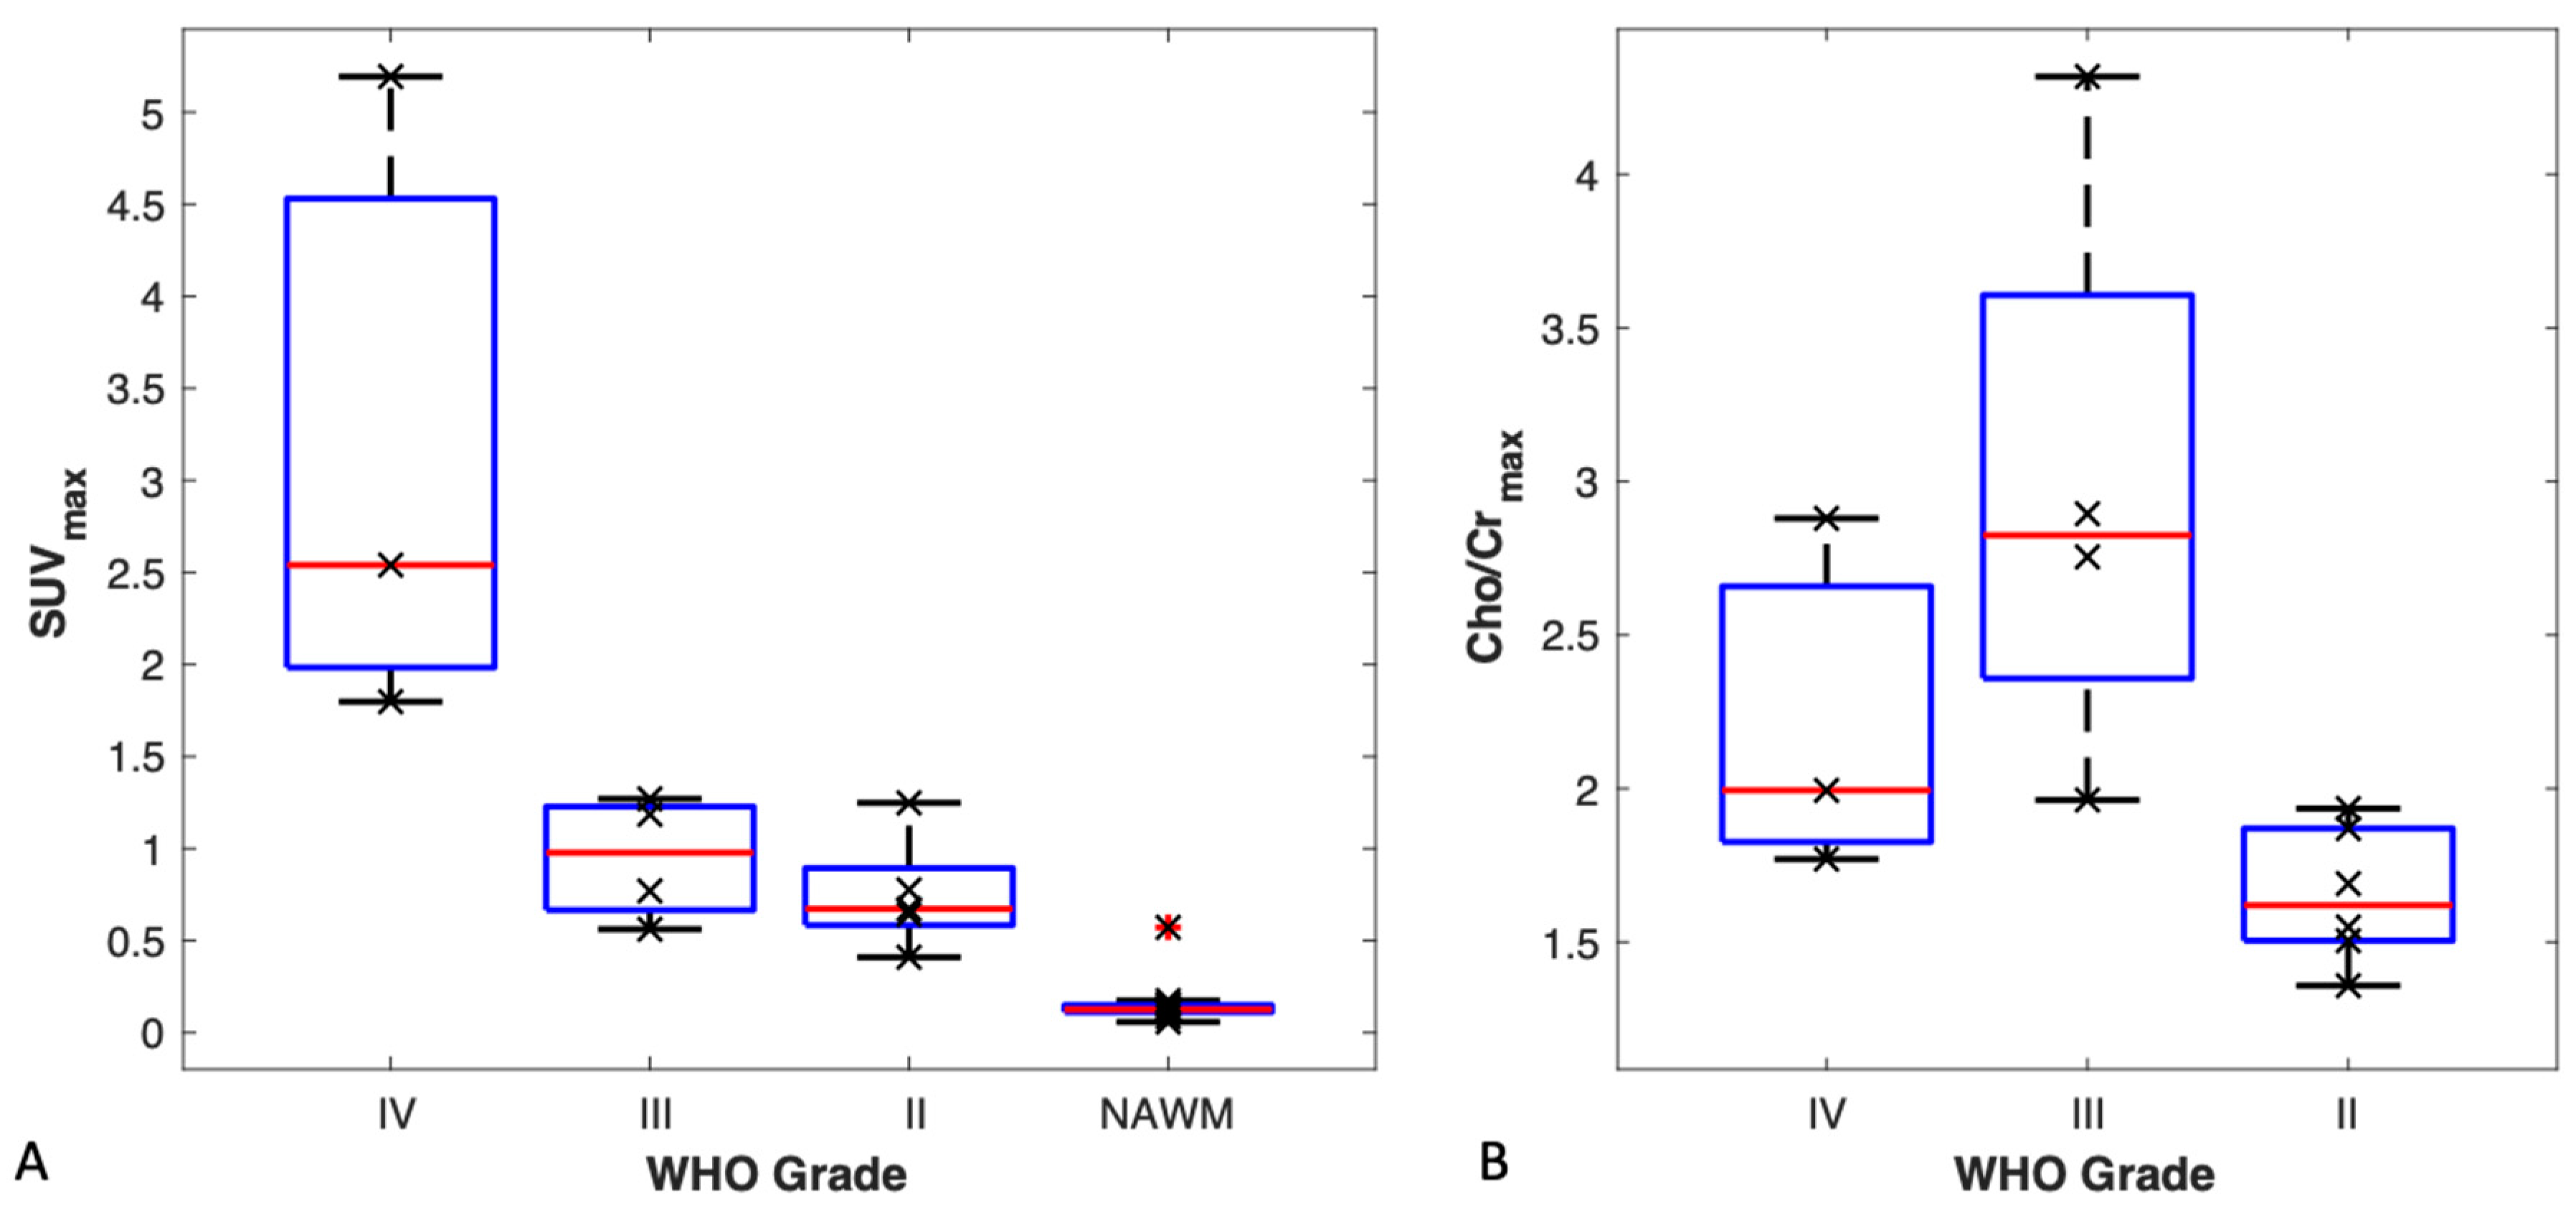

3.4. TBR and SUVmax vs. Tumour Grade

3.5. MR Spectroscopy vs. Tumour Grade

4.2. 18F-FMC Uptake and Cho/Cr in Glioma Grading